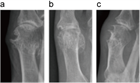

1. 痛風の確定診断は関節液中の白血球に貪食された尿酸―ナトリウム結晶の検出による(推奨度2)(JG)[1]